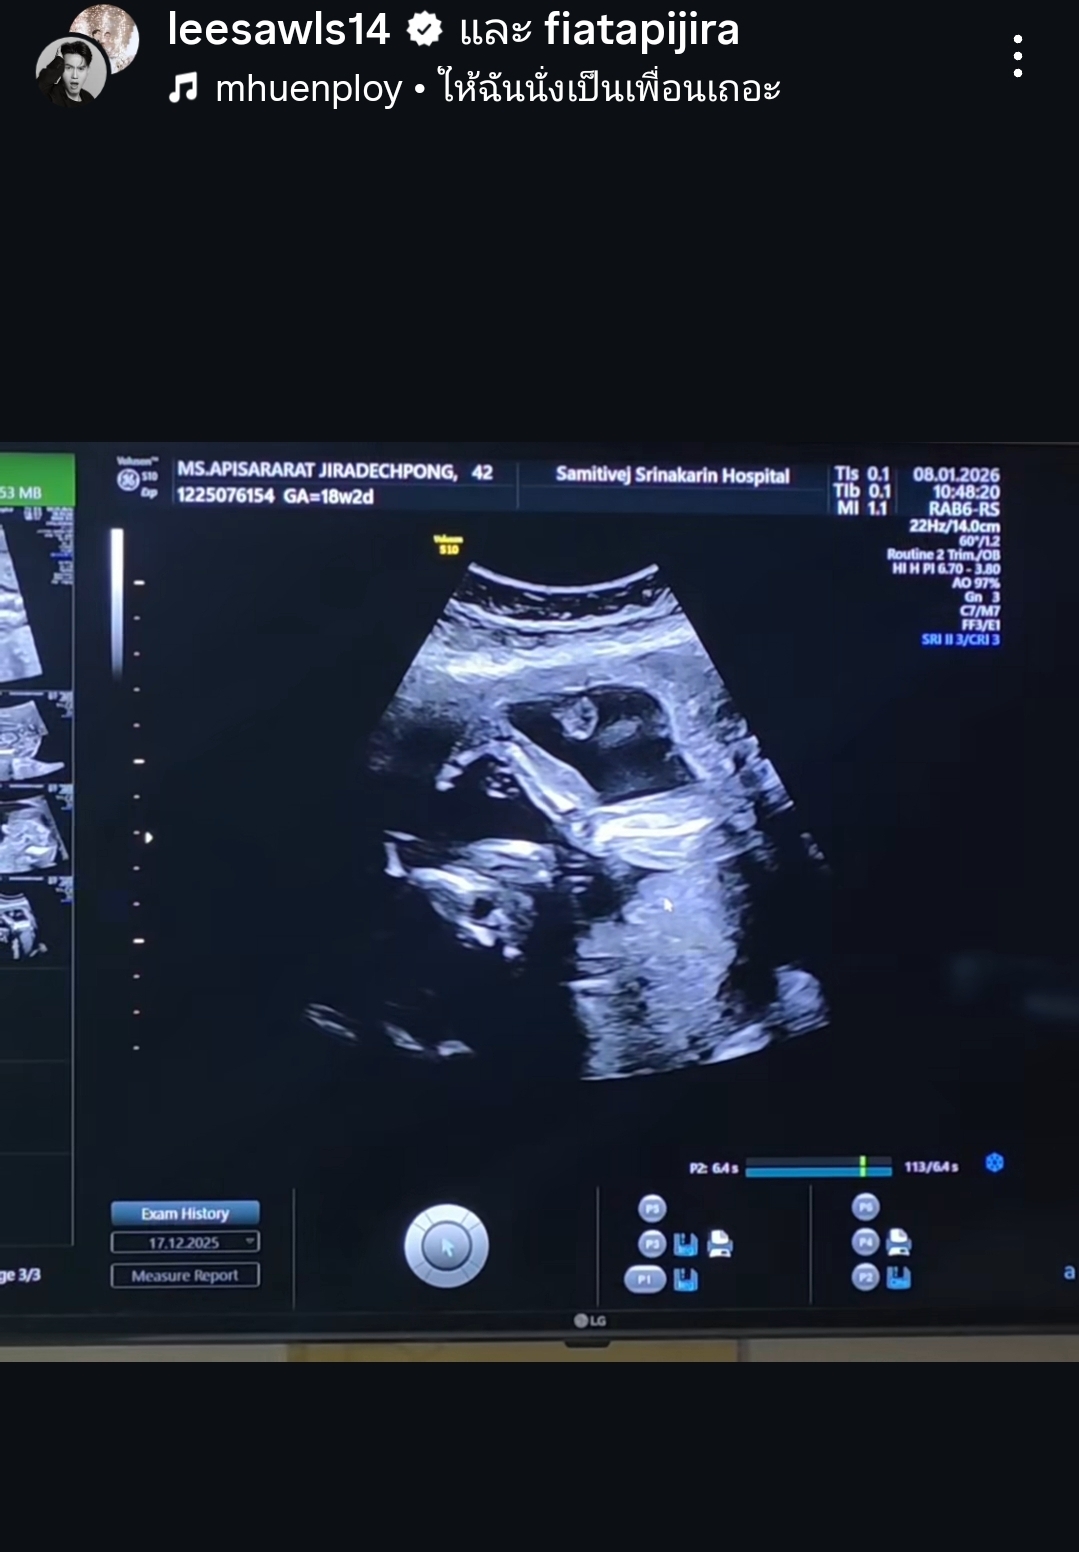

งานนี้ภาพอัลตร้าซาวด์ 4 มิติวัย 18 สัปดาห์บอกเลยว่าชัดแจ๋วแหว๋ว! เห็นถึงพัฒนาการที่ยอดเยี่ยม แขนขาลีบยาวจนฉายแววนักกีฬามาแต่ไกล ทำเอาคุณพ่อลีซอถึงกับยิ้มแก้มปริ โพสต์ภาพอวดชาวโซเชียลพร้อมติดแฮชแท็กประจำตัว #LFbaby จนเพื่อนร่วมวงการพากันเข้ามาส่งหัวใจให้รัวๆ